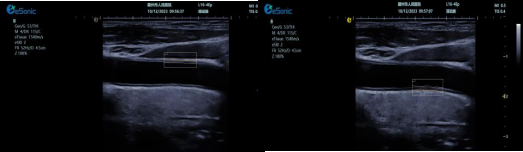

mFlowTM 超微血流显像技术

mFlowTM 超微血流技术在小型机器上率先实现微米级细小血管识别与低速血流捕捉,以往仅高端台式机具备此功能。该技术专注于颈动脉粥样硬化斑块内血流评估,无需造影剂,具有高分辨率、低运动伪像和高帧频成像特点。其优势如下:

image.png

? 运用 3D 壁滤波技术智能分析信号,可探测常规超声难以捕捉的低速血流,灵敏度高。

? 依据 Staub 标准对检查结果分级,直观展示斑块内新生血管血流,为斑块稳定性评估提供新指标。

? 基于多普勒原理,进行频谱测量并可进行VI指数测量,定量评估斑块内新生血管占比。

? 相较超声造影成像,无创便捷,为颈动脉易损斑块评估开辟新途径。